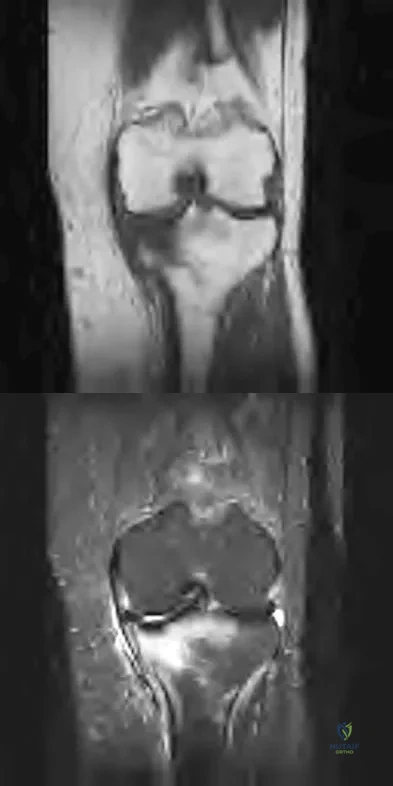

A 47-year-old male tennis player has pain in his nondominant shoulder that has failed to respond to 4 months of nonsurgical management. Examination reveals acromial tenderness and pain at the supraspinatus tendon insertion. He has a positive impingement sign, pain on forward elevation, and minimal cuff weakness. The MRI scans are shown in Figures 30a and 30b. To completely resolve his symptoms, treatment should consist of

Explanation